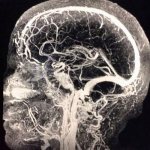

Происходит сужение сосудов эндометрия матки, вследствие чего кровоснабжение ее уменьшается. Слизистая оболочка начинает постепенно расслаиваться и отделяться от матки. Ее остатки выводятся наружу совместно с кровью, которая скапливается из-за разрывов мелких сосудов.

Врач может заподозрить остеопороз, если перестают нормально полноценно развиваться фолликулы, а значит, плохо синтезируются эстрогены (женские половые гормоны). Впрочем рецепторы, восприимчивые к ним, есть не только в костях, но и в волосах, коже, стенках сосудов, головном мозге, слизистых покровах. Поэтому от гормонального сбоя страдают все органы. А значит, решение любой проблемы со здоровьем женщине нужно начинать в кабинете гинеколога. Это сэкономит и силы, и время, и деньги.